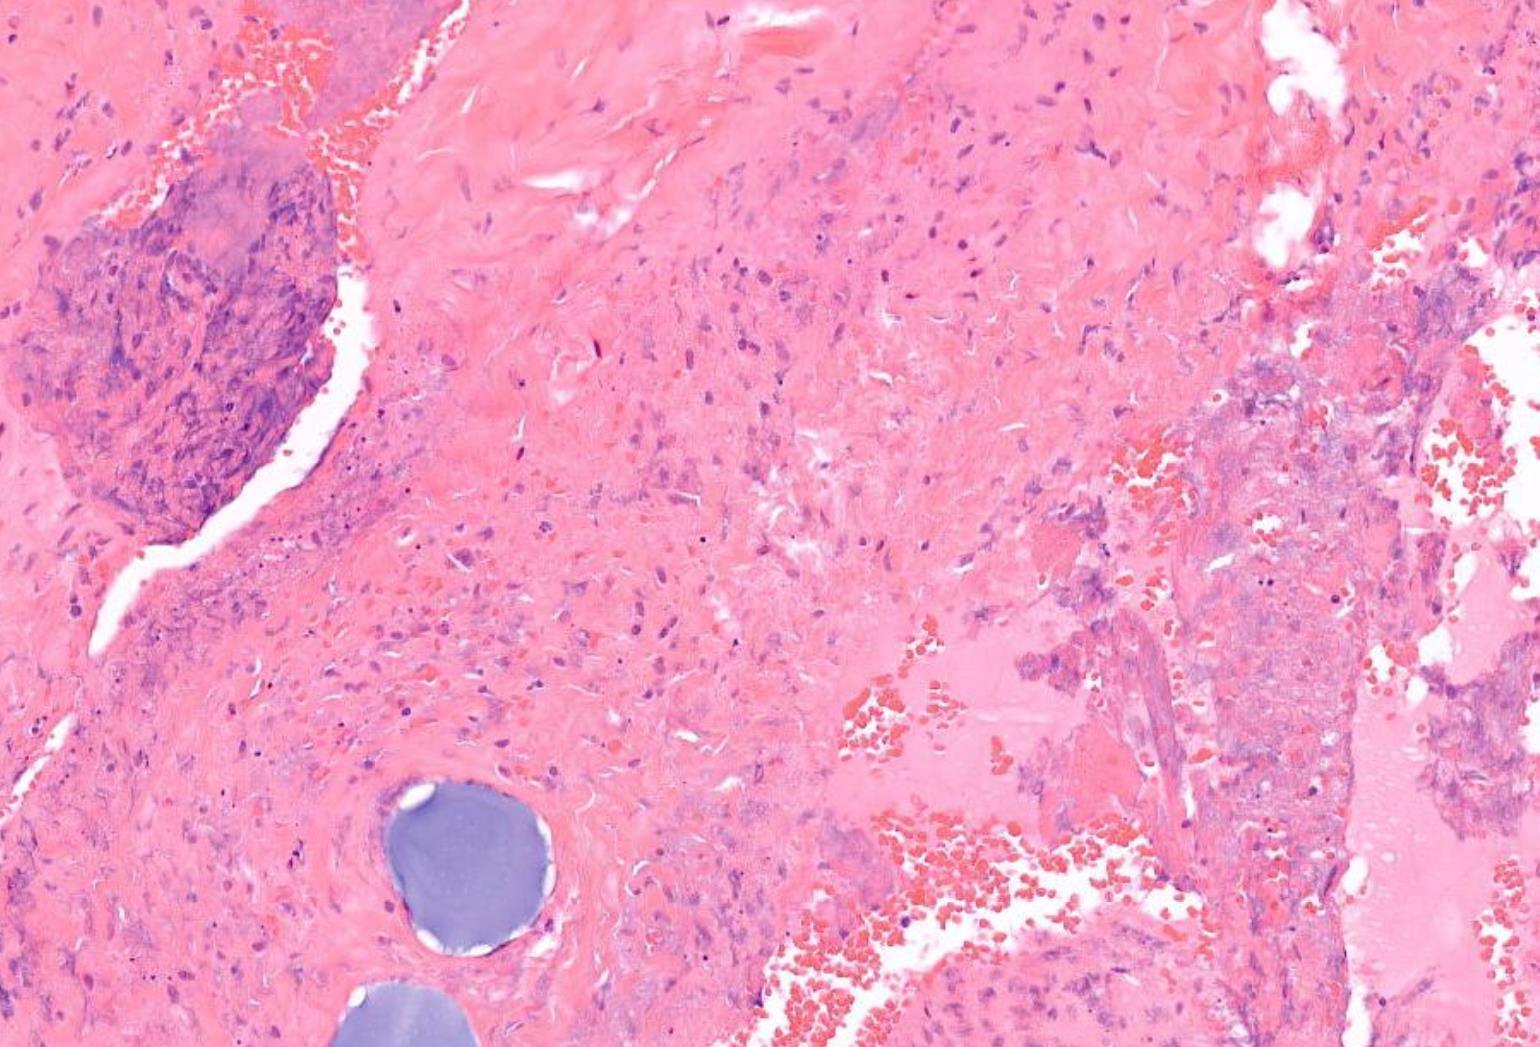

• Female 24 years

Lesion left forehead with a 6-8 week history of recurrent headaches. ? cause.

Specimen: Skull. Macroscopic description: Disc of bone covered on one surface by elevated soft tissue. Cut sections reveal a central bone cavity filled with granular material. -

Case 13

??

Case 13 Diagnosis

Langerhans cell histiocytosis

• Langerhans cell histiocytosis (LCH) is a clonal neoplastic proliferation of myeloid dendritic cells expressing LC phenotype • Single system/ multisystem involvement • cranial and facial bones, skin, gingiva, or cervical lymph nodes • intra-osseous ill-defined unilocular radiolucency with gingival involvement and tooth mobility. • >99% survival for unifocal disease LCH cell clusters are diagnostic, but caution is needed in lymph nodes because paracortical dendritic/LCs are indistinguishable from sinus-based LCH cells.